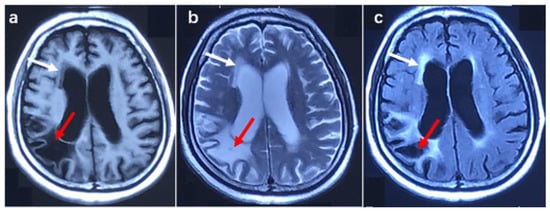

| Patient.No | Gender | Onset Age (y) | Site of Onset | Diagnosis Delay (mo) | Duration of Disease (mo) | ALS-FRS | NOTCH2NLC Repeat Size |

|---|---|---|---|---|---|---|---|

| 1 | male | 50 | Right lower limb | 30 | 35 | 34 | 46 |

| 2 | female | 62 | bilateral upper limbs | 6 | 30 | 40 | 45 |